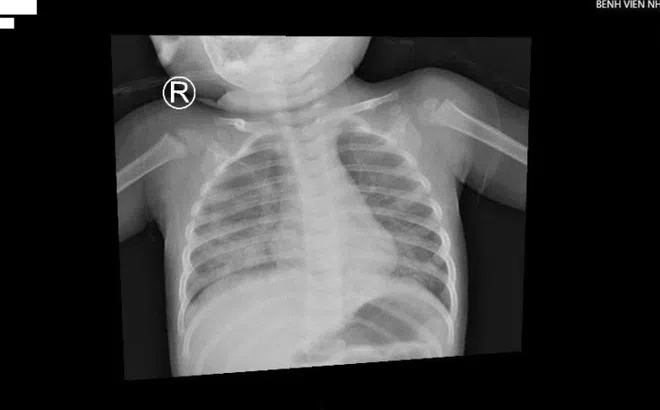

Bé trai 1 tuổi ở TP.HCM nhập viện vì hít dầu để thắp đèn

Nhập viện trong tình trạng khó thở, tím tái, bệnh nhi được chẩn đoán viêm phổi, tổn thương lan toả 2 phế trường gây suy hô hấp nặng.